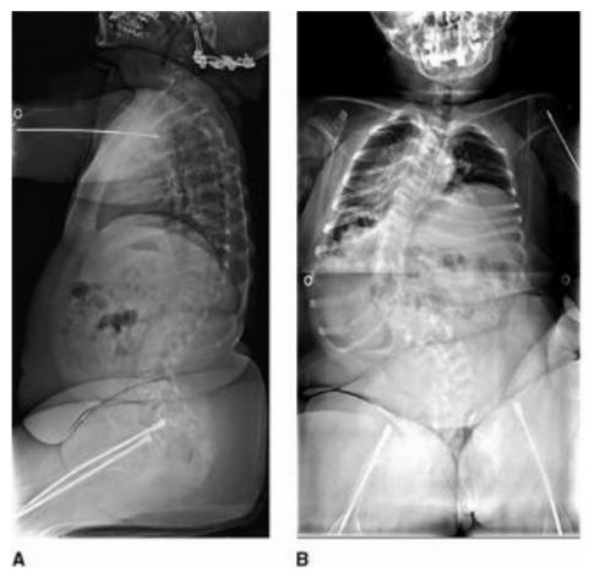

❖ Cột sống: Đốt sống thường loãng và hay bị xẹp, lỏng các phức hợp dây chằng dẫn đến các biến dạng như vẹo, gù. Vẹo cột sống gặp khoảng 20 – 40% bệnh nhân, thường gặp đoạn cột sống ngực Một số bệnh nhân sẽ có trượt đốt sống tiến triển. Cột sống cổ có thể gãy hoặc mất vững nhưng hiếm, nhưng nếu biểu hiện có thể gây biến dạng cột sống cổ, chèn ép hạnh nhân tiểu não, thiếu sót thần kinh.

❖ Điều trị vẹo cột sống [5]

- Điều trị khó vì xương loãng và biến dạng thường nặng, tiến triển.

- Điều trị bảo tồn bằng nẹp không hiệu quả giảm vẹo tiến triển vì xương sườn dễ gãy. Một số bệnh nhân có thể cho đeo nẹp cột sống ngực đến xương cùng để cải thiện vận động.

- Điều trị phẫu thuật khi góc Cobb trên 35 độ ở OI thể nặng, Cobb trên 45 độ ở OI thể trung bình.

- Phương pháp: Dùng cấu hình vít nắn chỉnh đi đường sau đa số trường hợp, dùng đường trước với bệnh nhân rất trẻ để tránh hiện tượng trục khuỷu (crankshaft) do nếu hàn phía sau thì phần cột sống phía trước vẫn phát triển ở bệnh nhân trẻ.

- Điều trị phẫu thuật thường khó vì mổ lớn, mất máu nhiều, xương loãng.